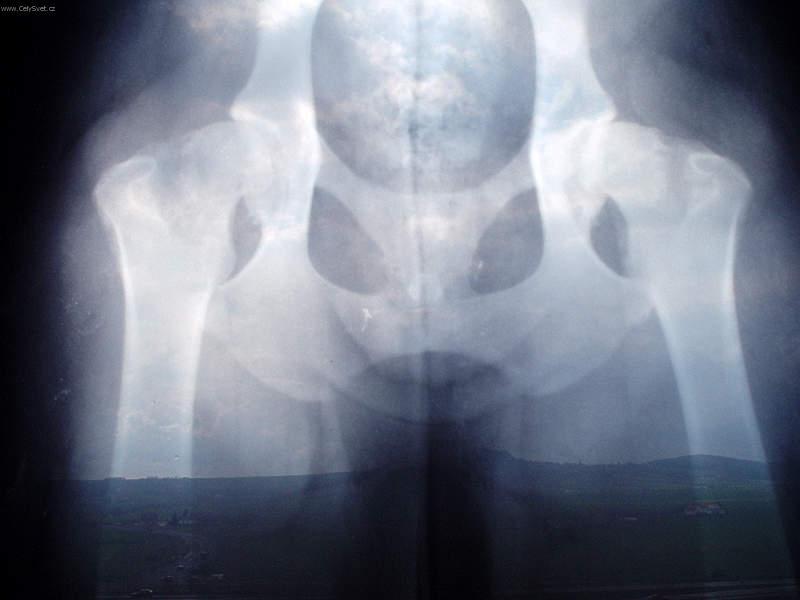

Fotogalerie > PSÍ SVĚT: Veterinární poradna > Ortopedie - DKK(www.celysvet.cz)Zobrazeno: 1193x (Datum vložení: 30.12.2005 000 18:51)www.CelySvet.cz > |